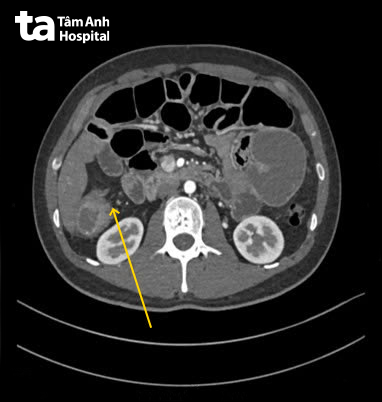

Tại Phòng khám Đa khoa Tâm Anh Quận 7, anh Công được chỉ định làm các xét nghiệm cận lâm sàng để kiểm tra. Kết quả chụp CT 100.000 lát cắt ghi nhận, giãn đại tràng phải và manh tràng 6,2 cm, giãn các quai ruột non 4,8 cm. Vị trí chuyển tiếp ở đại tràng góc gan dày thành khu trú 1,8 cm, một đoạn ruột 5 cm mất cấu trúc, bắt thuốc mạnh, thâm nhiễm mỡ nhẹ xung quanh và một số hạch nhỏ xuất hiện quanh tổn thương. Kết quả nội soi cho thấy, đại tràng góc gan có khối u sùi làm hẹp lòng, máy soi không qua được. Kết quả sinh thiết mô bệnh học chẩn đoán ung thư đại tràng góc gan, tế bào ung thư xâm lấn sâu, rộng làm tắc ruột gây ra các cơn đau ngực.